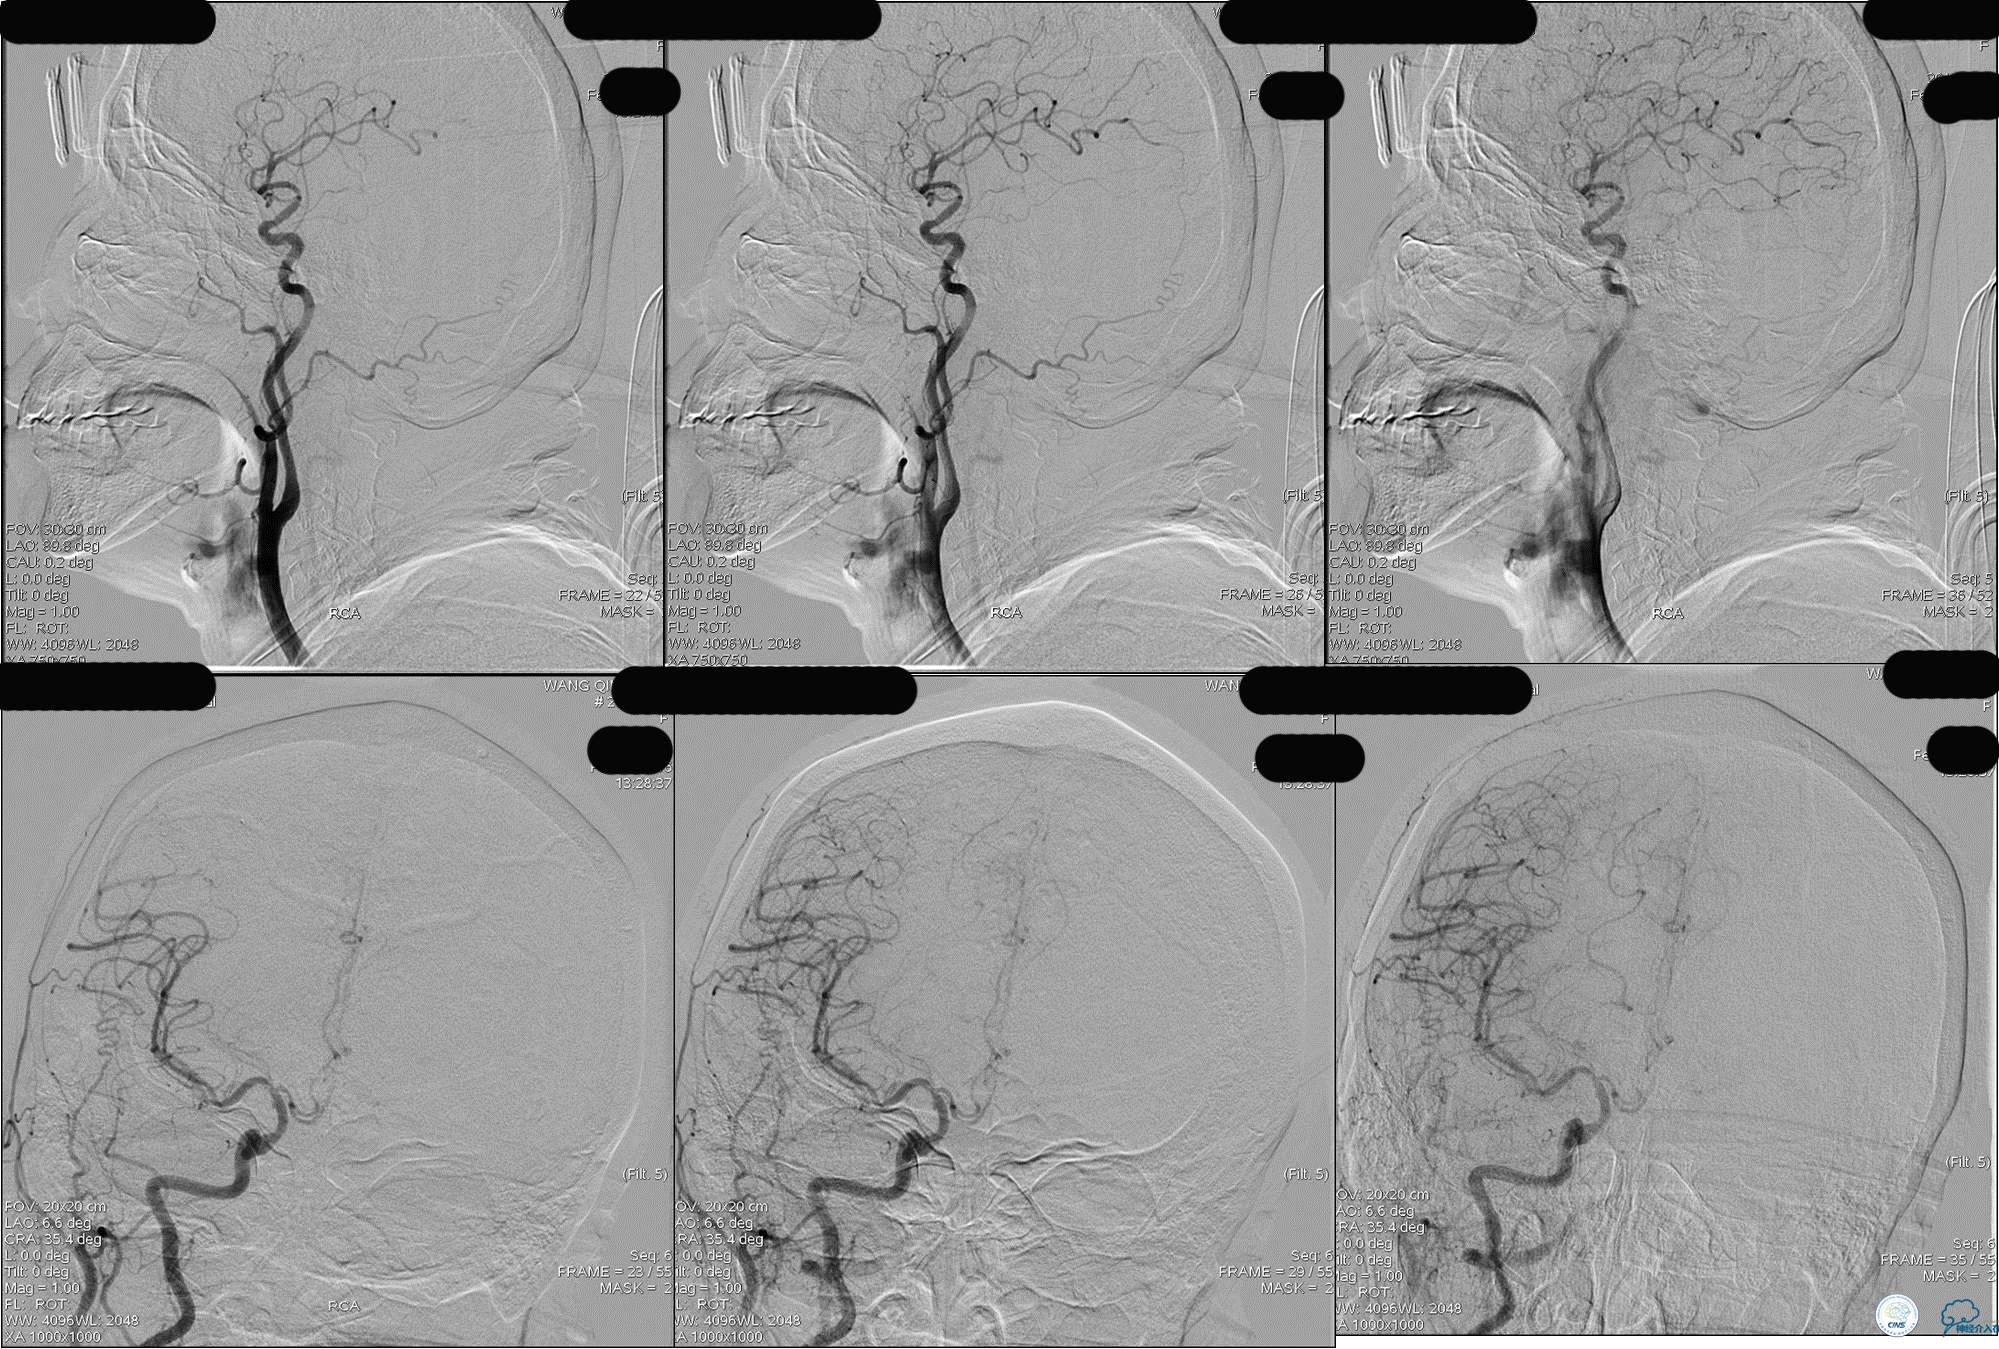

》DSA资料(右侧椎动脉)

》DSA资料(经桡动脉,5F导引导管)